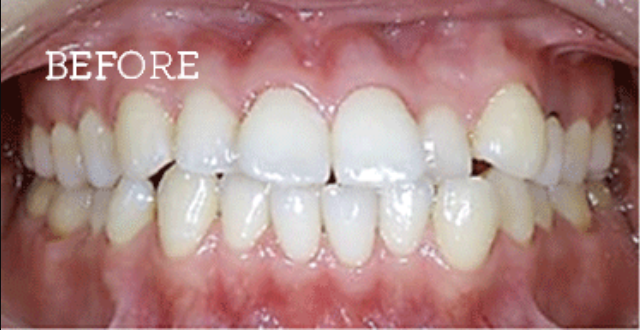

健康な歯をできるだけ残した矯正治療

当院では非抜歯の矯正も可能です。(※審美性を優先する場合は抜歯が必要な場合もございます。)

治療方法としては、歯列の幅を広げて隙間を確保し、歯を揃える手法を採用しています。特にV字型や方形型の歯列の方は、非抜歯でも矯正可能な方が多いです。

患者様のご要望に合わせて、最適な提案を行い、納得いただいた上で治療を進めるよう努めています。